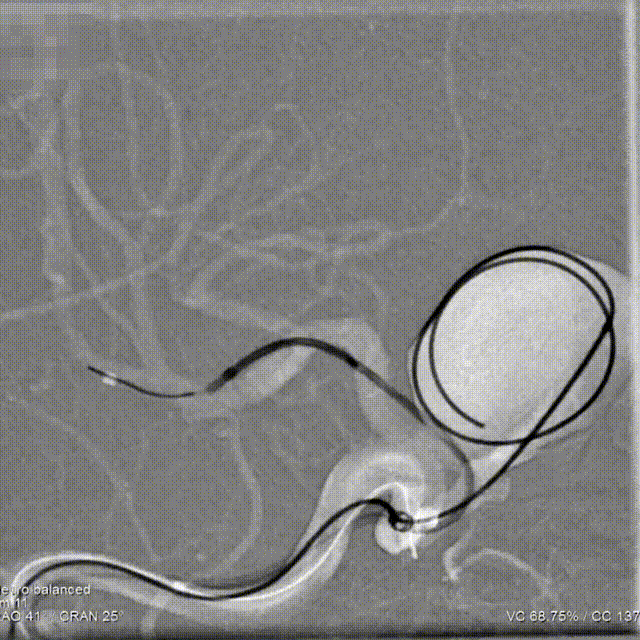

手术过程

Step1:微导丝&微导管成袢技术到达远端血管建立通路,采用交换技术交换微导丝&微导管,200cm微导丝到达M2段,缓慢输送Fastrack 27(0.027inch)支架导管到达M1段。

Step2:支架导管到位后,再次测量动脉瘤远近端血管直径&预释放长度等信息,确认支架规格选择是否匹配。输送弹簧圈微导管到达动脉瘤囊内预埋填塞位置。

Step3:预埋弹簧圈不解脱,输送Tubridge Plus 4.0mm*30mm支架到位、并缓慢回撤支架张力使支架头端打开呈“V”型,缓慢回撤支架到达预释放位置,并造影确认。

Step4:远端锚定与释放;为使支架在瘤颈口处稳定的释放,远端采用较长的锚定长度。并通过回撤支架导管与轻微推挤支架张力的动态平衡方式,使Tubridge Plus前端50%区域的每个节段与血管壁充分贴合。

Step5:弯段释放;支架远端打开稳固后,采用缓慢推挤支架给张策略进行释放,最终使得支架中后端在弯段处充分打开与贴壁。

Step6:支架按摩;支架整体释放完毕后即刻采用“J”型导丝,由远至近对Tubridge Plus支架的每个节点进行充分按摩,使其保证支架每个节段与血管壁充分贴合。

Step7:持续完成弹簧圈栓塞,评估瘤颈口造影剂滞留程度。

Step8:术后即刻工作位造影,可见瘤颈部位及囊内血流滞留明显,支架打开、贴壁良好。